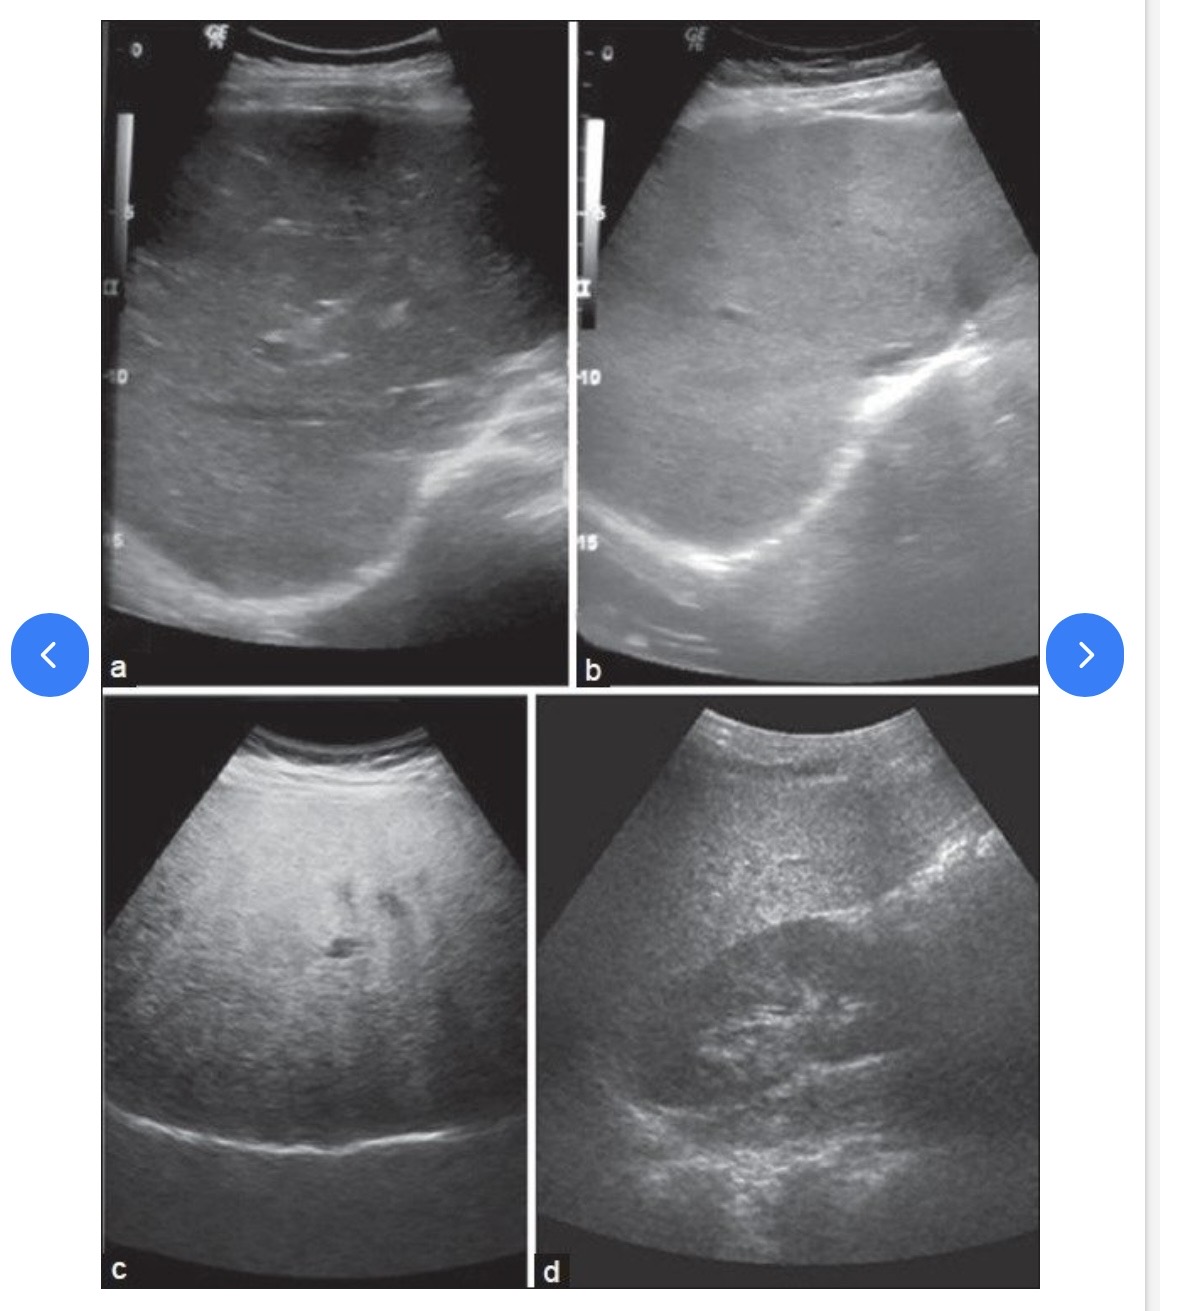

Grades of fatty liver on visual analysis. Ultrasound image shows (a) Normal liver echogenicity (b) Grade 1 fatty liver with increased liver echogenicity (c) Grade 2 fatty liver with the echogenic liver obscuring the echogenic walls of the portal venous branches (d) Grade 3 fatty liver in which the diaphragmatic outline is obscured

Fatty liver should be charted as echogenic liver. Difficult to penetrate. Consistent with Fatty liver.